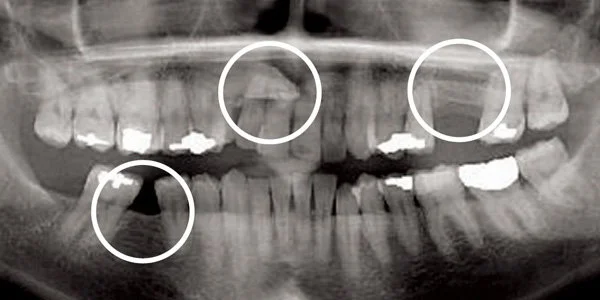

Impacted/Missing Teeth

X-ray shows problem areas